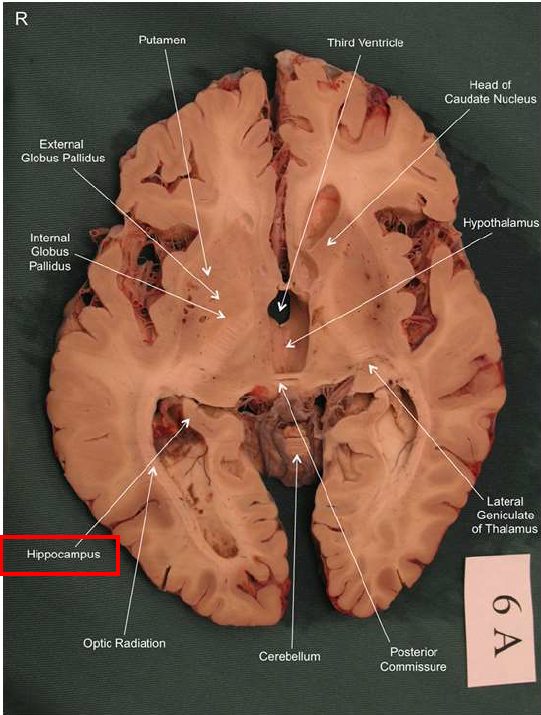

What is this?

hippocampal fornix